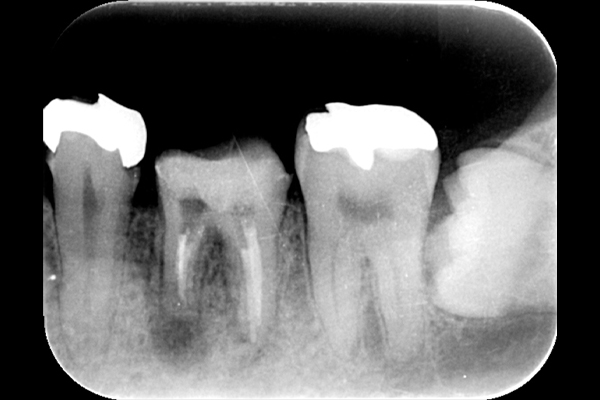

肉眼では根の先端は見ることができませんがマイクロスコープでは見ることができます。根の先端をこれ以上破壊しないように清掃して歯の神経があった場所にお薬を詰めることができました。根の治療後、かぶせ物までして半年たっても痛みがありません。

レントゲンを見ていただいて、歯の先までしっかり白いお薬が入っているのがわかります。

| 根の中の薬が十分に充填されておらず、根の先が周りと比べて黒くなっており、炎症があると判断できます。 | 根の中にしっかりとお薬を緊密に充填しましたが、まだ根の先に黒くなっている部分があります。 |